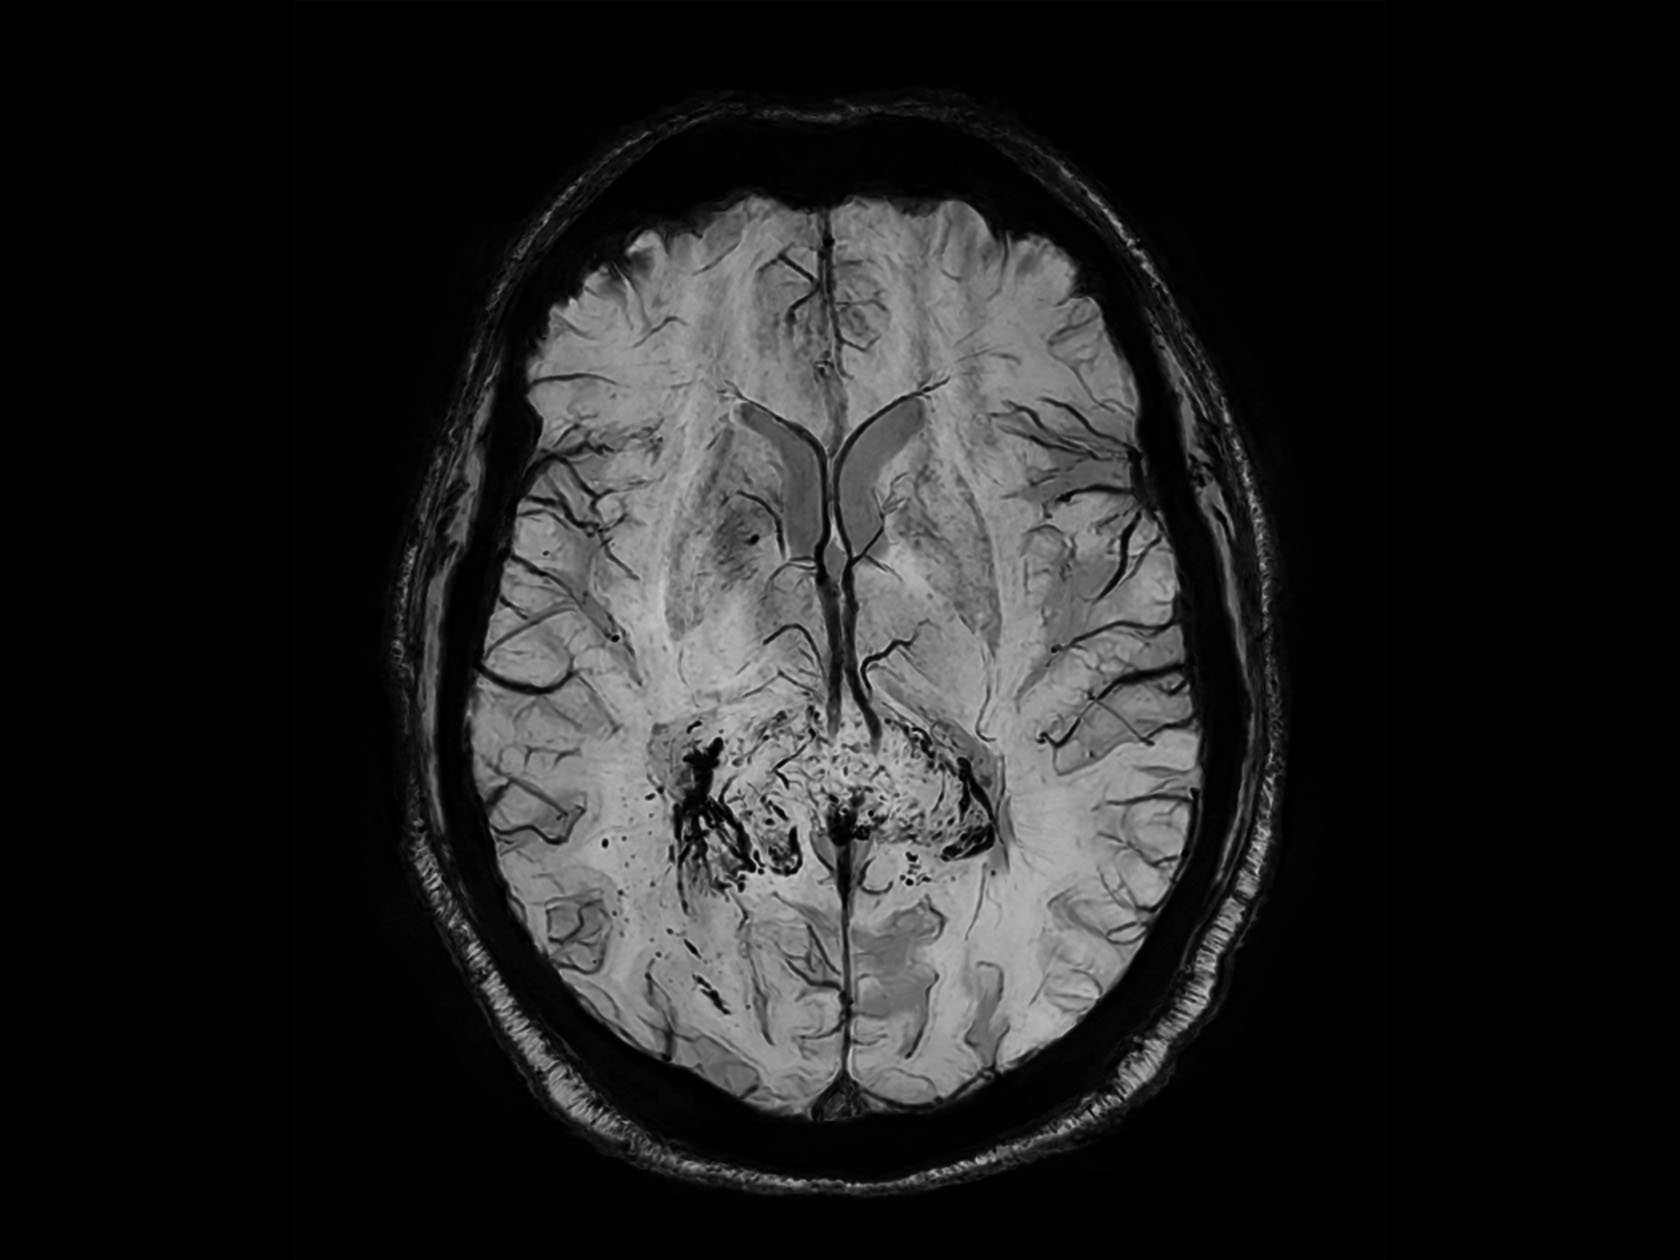

Axial T2w TSE with FatSat

-